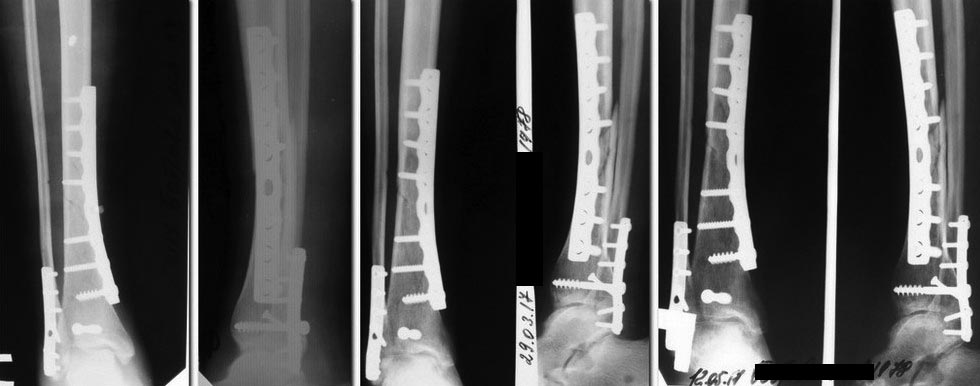

Уважаемые коллеги, помогите по тактике лечение. Девушка 39 лет,работающая, без вредных привычек, состояние после остеосинтеза костей голени от 20.12.2016.

Травма бытовая 12.12.2016, 20.12.2016 выполнена открытая репозиция остеосинтез большеберцовой кости пластиной, заднего края ДМЭ винтом, синтез наружной лодыжки пластиной. Рентгенограмм до операции нет. До прошлой недели ходила на костылях без нагрузки, принимала остеогенон. В январе курс реабилитации. В настоящий момент клинически - отека нет, п/о рубец без патологии, пальпация голени безболезненна. Движения в коленном суставе в полном объеме, небольшое ограничение тыльной флексии в голеностопном суставе. Разрешена нагрузка 20-25 кг (до 50% массы тела), 3 дня в таком режиме - новых жалоб не появилось. Мнения по дальнейшему ведению разделились.

1 вариант - продолжить ЛФК, физиолечение, медикаментозную терапию с дозированной нагрузкой. Подождать до еще хотябы 3 мес. 2 вариант - оперативное лечение с костной пластикой.